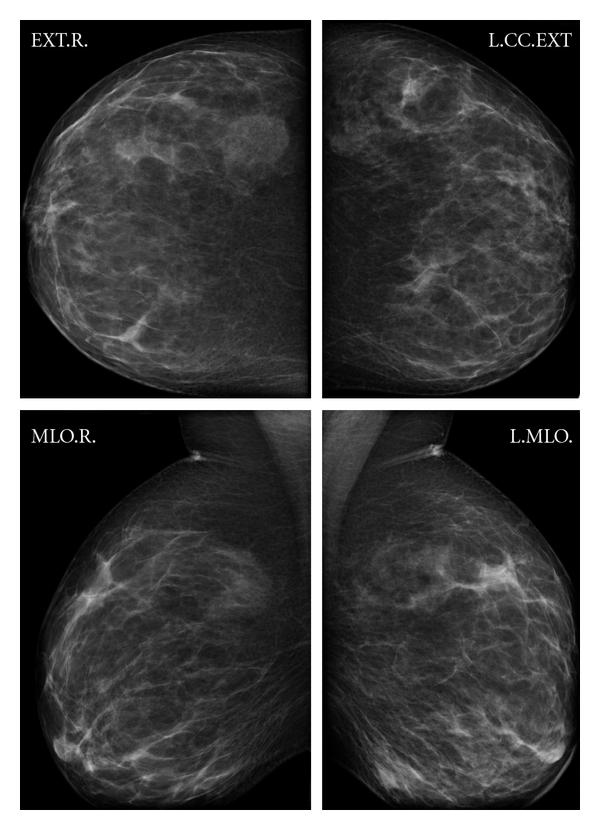

mammographyLa mastografía es una prueba de diagnóstico por imagen que se utiliza para detectar posibles anomalías en las mamas, especialmente el cáncer de mama. Durante la prueba, se toman imágenes de alta calidad de las mamas, utilizando equipos de rayos X especialmente diseñados para este propósito.

La mastografía busca detectar cualquier alteración en las mamas, como bultos, masas, calcificaciones o cualquier otro signo que pueda indicar la presencia de cáncer de mama u otras enfermedades mamarias. Además, también se busca detectar cualquier cambio en las mamas que pueda indicar un problema en el tejido mamario, como quistes o fibroadenomas.

La mastografía es realizada mediante la utilización de un equipo radiográfico especializado, que emite rayos X de baja dosis a través de las mamas. Las imágenes resultantes son estudiadas por un equipo de profesionales altamente capacitados, quienes buscan identificar cualquier tipo de anormalidad que pudiera ser indicio de una patología mamaria.